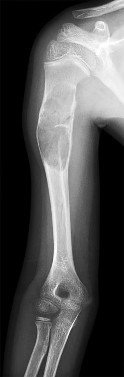

ORTHOPEDIC MCQS ONLINE 20 OB TRAUMA 1D fractures is associated with decreased shoulder strength and increased…